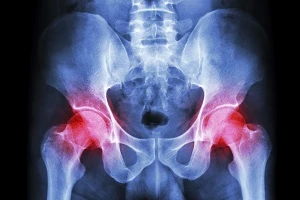

The types of devices that are considered high-risk are devices are implanted in the body or support human life. This means that devices like hip replacements, intraocular lenses and coronary stents receive very little scrutiny before being used in patients.

None of the devices studied have caused the death of any patients. One was voluntarily recalled because of a flaw that could be potentially deadly, and thousands of patients implanted with DePuys Pinnacle Complete prosthetic hip replacement have sued the company for adverse side effects.